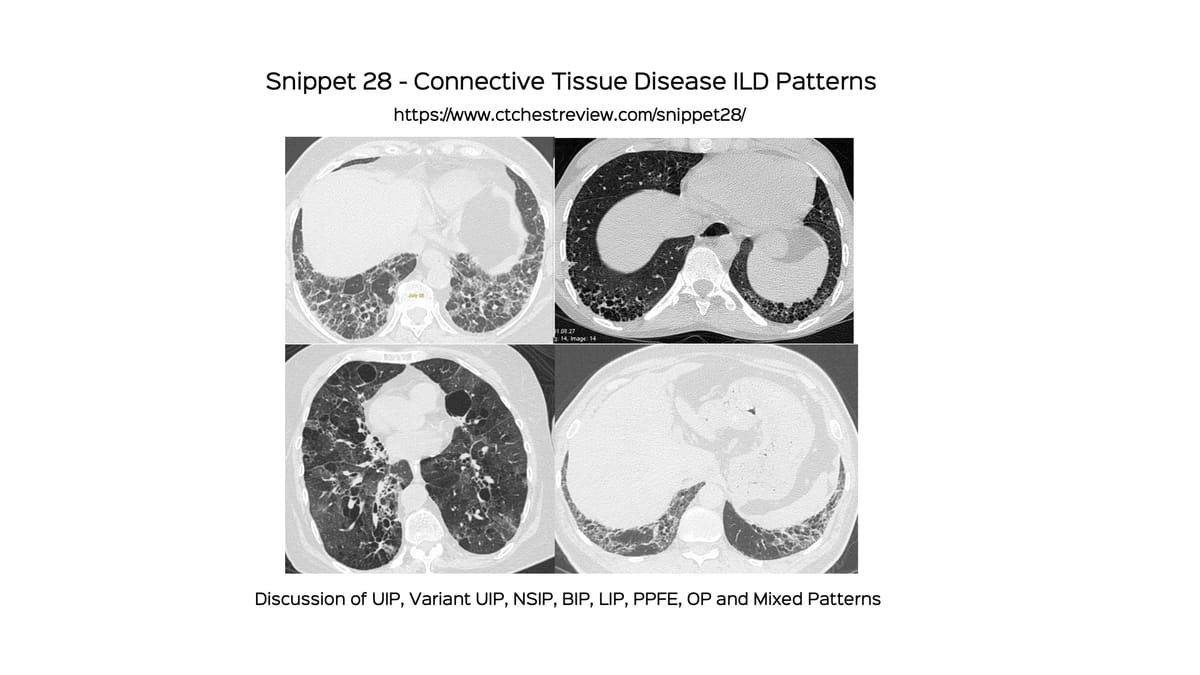

This complements the earlier post on Connective Tissue Disease ILD Patterns, where I did not discuss "mixed patterns" in detail and the previous post titled "Mixed Patterns in Connective Tissue Disease ILDs" as well as last month's post titled "Decoding DPO and CiOP"